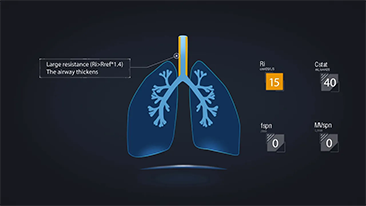

Bien dÊfinir les rÊglagesdu ventilateurpour le traitement des patients souffrant de maladies des voies respiratoires est une question très importante. Comme il incombe au mÊdecin de spÊcifier les paramètres de l'Êquipement de ventilation, ses connaissances et son expÊrience en matière de sÊlection de cesrÊglages ont un effet direct sur l'exactitude de ses dÊcisions. Le paradigme des soins de soutien aux patients a considÊrablement changÊ au cours des 20 dernières annÊes. Aujourd'hui, divers modes de ventilation et outils d'aide à la dÊcision ont ÊtÊ dÊveloppÊs autour des besoins cliniques pour aider les soignants à amÊliorer leur efficacitÊ et à Êliminer les erreurs dans les dÊcisions cliniques.

Combinant oxygĂŠnothĂŠrapie Ă haut dĂŠbit (OHD), ventilation non invasive (VNI) et ventilation invasive (VI) les ventilateurs de la sĂŠrie SV 3 en 1 offrent des performances stables, des fonctions polyvalentes et une simplicitĂŠ d'utilisation. Des caractĂŠristiques exceptionnelles de ventilation protectriceet de nombreux outils d'aide Ă la dĂŠcision sont con?us pour rĂŠduire le risque d'infection croisĂŠe et faciliter le travail quotidien du personnel soignant.